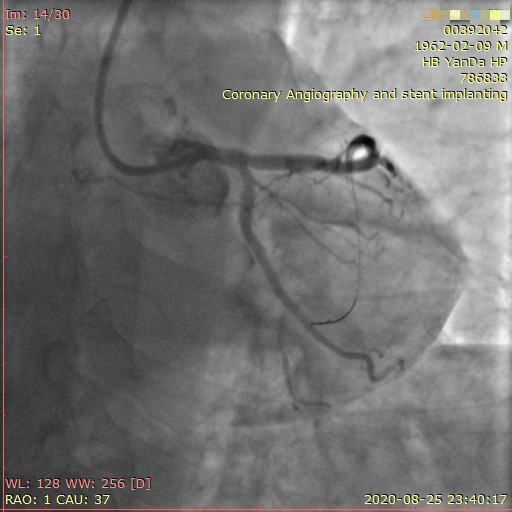

李先生右冠術(shù)前影像

術(shù)前,翟光耀主任還親自為李先生復(fù)查冠狀動脈造影,造影結(jié)果顯示:患者的前降支、回旋支、右冠等冠脈三支嚴(yán)重病變、嚴(yán)重鈣化,且均為彌漫性長病變,最重處99%以上管腔極嚴(yán)重狹窄。翟主任仔細(xì)閱讀造影結(jié)果后指出:結(jié)合李先生的實際情況,雖然微創(chuàng)介入手術(shù)難度比較大,但仍可行;李先生心臟三支主干動脈均存在極其嚴(yán)重的狹窄,每一支動脈均至少植入2-3枚支架,根據(jù)患者的耐受情況,李先生可能需要分3次分別對三支動脈進行介入手術(shù);考慮到李先生路途遙遠(yuǎn),病情嚴(yán)重,不宜反復(fù)奔波,并且患者迫切要求能夠徹 底解決病痛,在病情允許的情況下,如果手術(shù)順利,爭取為患者進行“一站式”手術(shù),一 次 性解決全部三支動脈病變!